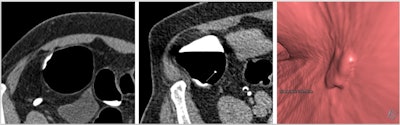

When performed to the highest quality, CTC has excellent diagnostic accuracy for clinically significant neoplasia -- i.e., colorectal cancer and advanced neoplasia -- in both symptomatic and screening populations. But unlike colonoscopy, substantial variations in practice exist in the U.K. and internationally, they added.

The guidance uses all available evidence to define optimum examination technique and standards of reporting including both minimum numbers of examinations to be reported by an individual and the time taken to report studies. "These are the performance indicators which allow us to evaluate our own departments and individual performance," he said.